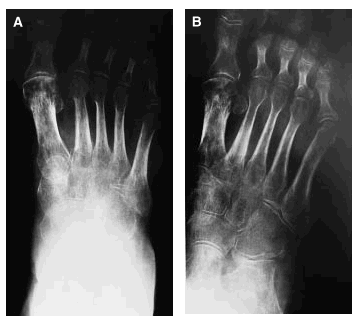

Se trata de una paciente de 58 años de edad, con antecedentes de osteoporosis, que tras sufrir una caída se practicó unas radiografías (figs. 1A y B) donde le encontraron una fractura de la falange proximal del primer dedo del pie derecho y un esguince de tobillo, por lo que le pusieron un tratamiento sintomático con lo que fue empeorando de su cuadro doloroso con limitación funcional, hasta 3 meses más tarde en que se practica una nueva radiografía (figs. 2A y B), donde se confirma una osteoporosis difusa con imágenes líticas, preferentemente en la articulación tibio-peroneo-astragalina, así como en calcáneo.

Figs. 1A y B